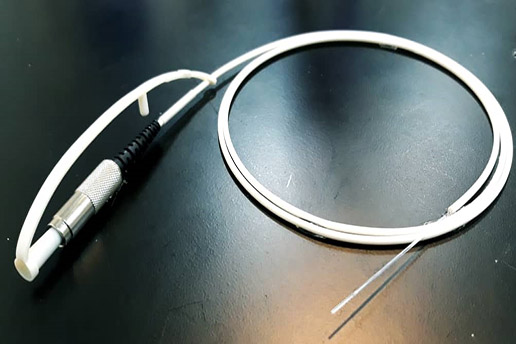

Diffused Fiber Laser Probe:

This specific laser fiber allows the treatment of a wider range of tumors with a single treatment and overcomes the limitations of currently available laser fibers, such as the limited achievable lesion sizes due the maximum power that can be used without carbonizing tissue.

Applications:

- Hemorrhoids and fistulas

- Tumor ablation

Clinical Tests has done by a group of specialized and sub-specialized in diseases and surgery of the.

Hemorrhoids and fistulas. This fiber is the best choice for tumor ablation and fistulas.

|

Core ф [µm] |

Clad ф [µm] |

Outer ф (fiber) [µm] |

NA |

Certifications & approvals: (In Progress)

Our production processes, devices and procedures is certified by ISO 13485 .

And Iran national medical device directorate (IMED)